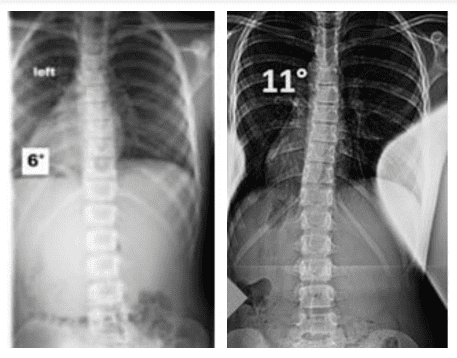

Got my x-rays done and turns out that I'm already withering away in muh 20s. Have mild osteochondrosis and have some osteophytes developing on my lower vertebrae. 15 degree lumbar scoliosis btw.

Yes, I have, when I was 20. The cobb angle remained the same but I'm just surprised that I have mild osteochondrosis. According to the jews, it's normal to have such a condition. Funny, since I spam weighted pull ups every other day and yet nothing good comes out of it. Seems like I'm just accentuating my muscle imbalances.

you can't fix scoliosis, you can partially reverse it.